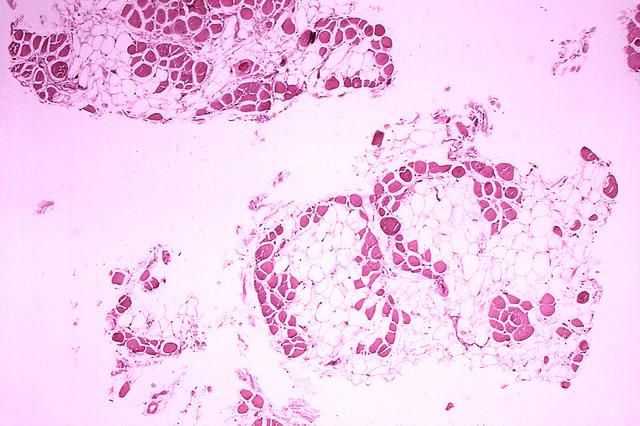

杜氏肌營(yíng)養不良癥患者的肌肉

Emma Kemp 使用Servier Medical Art制作的肌肉結構主圖和說(shuō)明 iPS 細胞在肌營(yíng)養不良癥細胞療法研究中的應用?。Edwin P. Ewing, Jr 博士拍攝的杜氏肌營(yíng)養不良癥患者的肌肉圖像,由美國衛生與公眾服務(wù)部公共衛生圖像庫提供?。Mike Kayser的肌纖維照片?,Wellcome Images。?